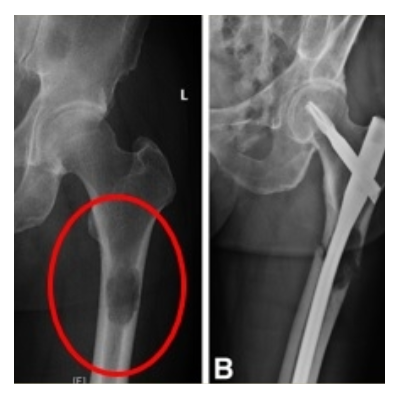

Long bone skeletal metastases are common in theUS, with more than 280,000 new cases every year.Clinical dilemma: whether the metastatic tumor hasweakened the bone

sufficiently such that apathological fracture is imminent. To answer thatquestion, physicians rely primarily on MirelsCriterion which has been criticized by MDsregarding its

ability to predict fractures. Simfini-TUMOR provides a reliable risk of fractureassessment to address this clinical dilemma. Hence.fewer unnecessary surgeries need be performed.